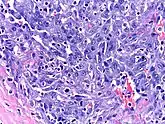

| Micrograph of HHV8-associated Castleman's Disease showing LANA-1 positive lymphoblasts in a regressed germinal center and mantle zone. LANA-1 stain. | |

Unlike the other subtypes of Castleman disease, UCD and iMCD, which can present with a spectrum of features on microscopic analysis (histology) of tissue biopsied from an enlarged lymph node, only a plasmablastic pattern of histologic features has been described in HHV-8-associated MCD. Plasmablastic features are similar to the plasmacytic features seen in iMCD and UCD, with both demonstrating increased plasma cells in interfollicular spaces. Plasmablastic features are differentiated from plasmacytic features by increased numbers of plasmablasts in follicular mantle zones.[10]

Staining with latency-associated nuclear antigen (LANA-1), a marker for HHV-8 infection, is typically positive.[11]